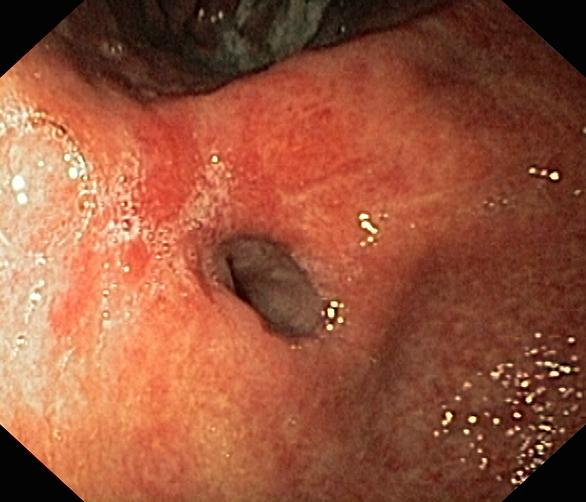

Wrzód trawienny